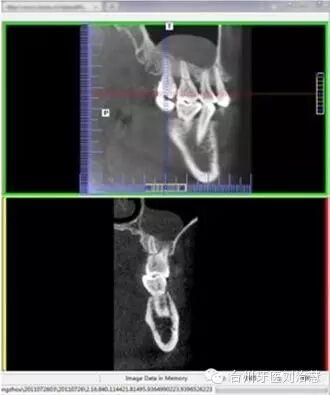

口腔CT,指的是CBCT,就是Cone beam

CT的简称,即锥形束CT。顾名思义是锥形束投照计算机重组断层影像设备,其原理是X线发生器以较低的射线量(通常球管电流在10毫安左右)围绕投照体做环形DR(数字式投照)。然后将围绕投照体多次(180次-360次,依产品不同而异)数字投照后“交集”中所获得的数据在计算机中“重组,reconstruction”后进而获得三维图像。

CBCT与体层CT(螺旋CT)的最大区别在于体层CT的投影数据是一维的,重建后的图像数据是二维的,重组的三维图像是连续多个二维切片堆积而成的,其图像金属伪影较重。而CBCT的投影数据是二维的,重建后直接得到三维图像。从他们的成像结构看,CBCT用三维锥形束X线扫描代替体层CT的二维扇形束扫描;与此相对应,CBCT采用一种二维面状探测器来代替体层CT的线状探测器。显然,CBCT采用锥形束X线扫描可以显著提高X线的利用率,只需旋转360度即可获取重建所需的全部原始数据。因此,患者接受射线大大减少。

总之,CBCT数秒内完成对患者的扫描,实现对种植位点的快速评估,并使用嵌入工具测量可以利用的骨量,发现隐藏的病灶。使用自动神经管标记工具描绘出神经管走行。直观显示骨内阻生牙的精确位置,确定临牙位置及毗邻重要结构,包括神经管、上颌窦壁和骨皮质边界。

CBCT卓越的清晰度和细节显示根尖、牙冠、切端和上颌窦等各个解剖结构。对特定解剖结构的智能重建能够为每位患者自动创建最优的个性化图像。